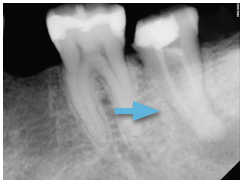

This clinical photo of the canals demonstrates the C-shaped nature of the anatomy. To aid in the disinfection process, Calcium hydroxide (Ca(OH)2) was placed as an inter appointment medicament for approximately 10 days.

The radiopaque paste in the canal is the Ca(OH)2, which acts as a local antibiotic inside the tooth, to remove the source of the infection, bacteria.